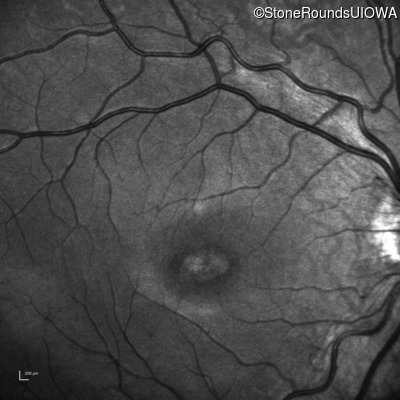

Infrared Fundus Photograph - Right - 20/80 -2 sc

Exemplar